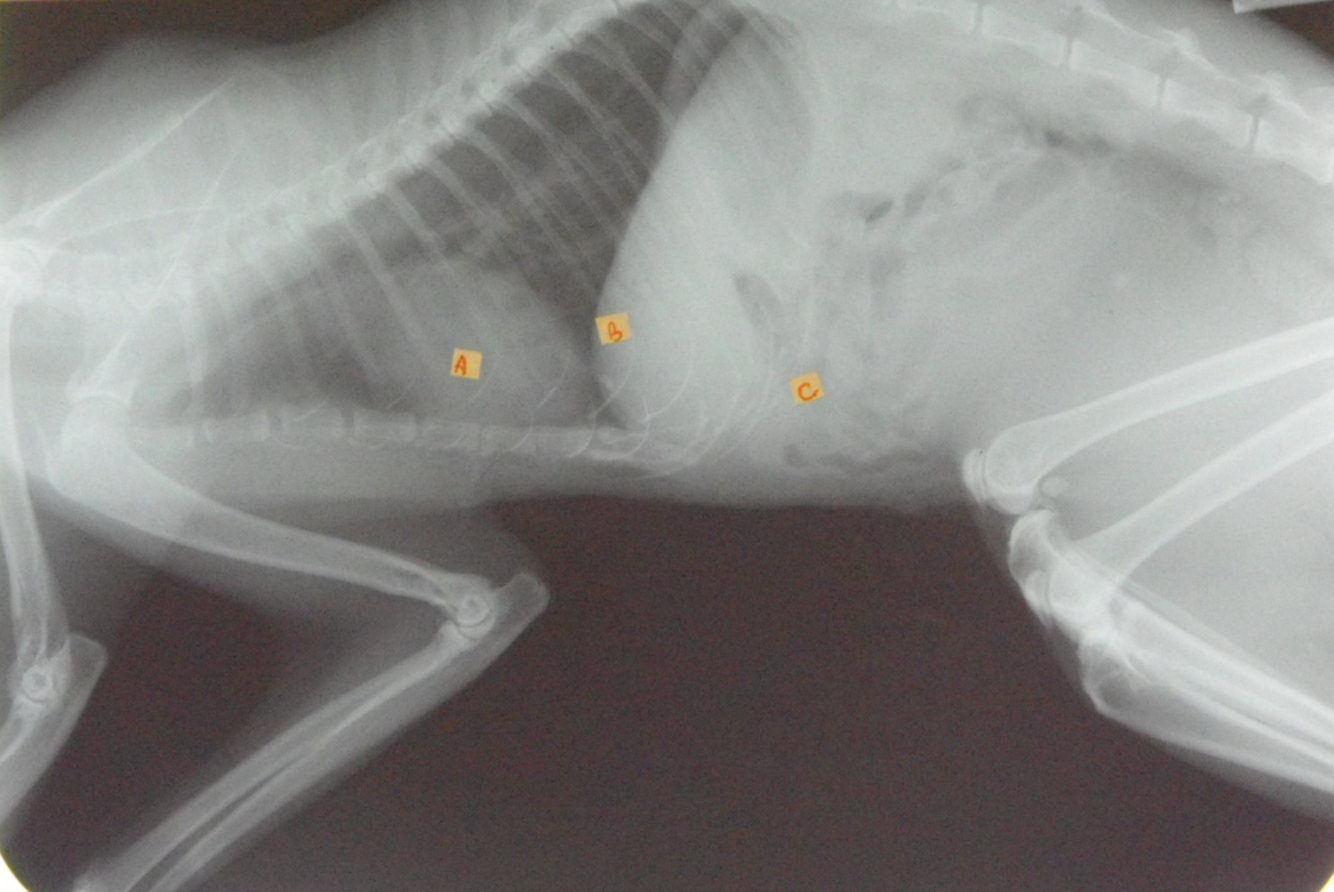

identify A, B and C

A= left atrium

B= right ventricle

C= trachea

identify the structures of the cat thorax

A= heart

B= diaphragm

C= liver